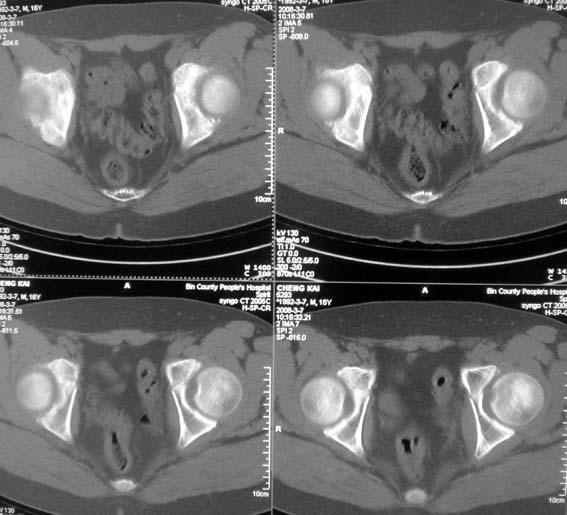

男,16岁,髋部疼痛,发育延迟。

考虑:双侧髋臼发育不良性骨病。

双侧髋臼发育不良性骨病

双侧髋臼发育不良性骨病.股骨头早期坏死?

双侧髋臼发育不良性骨病(髋臼窝变浅,髋臼内上缘关节面毛糙)。

考虑:双侧髋臼发育不良性骨病